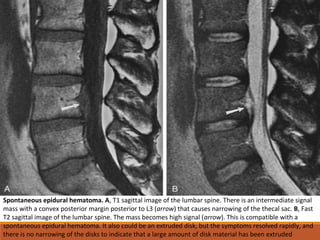

Spontaneous epidural hematoma. A, T1 sagittal image of the lumbar spine. There is an intermediate signal

mass with a convex posterior margin posterior to L3 (arrow) that causes narrowing of the thecal sac. B, Fast

T2 sagittal image of the lumbar spine. The mass becomes high signal (arrow). This is compatible with a

spontaneous epidural hematoma. It also could be an extruded disk, but the symptoms resolved rapidly, and

there is no narrowing of the disks to indicate that a large amount of disk material has been extruded